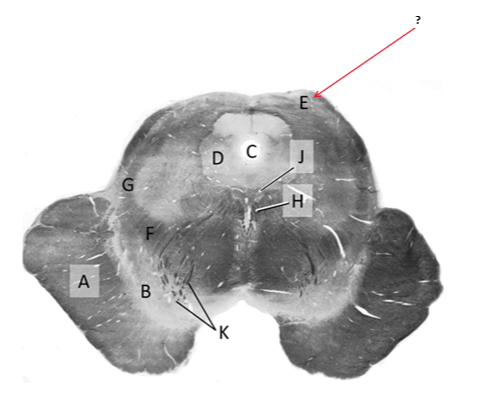

Name this and state its function.

Tectum.

Name this and its divisions+ function?

Substantia nigra.

Cerebral aqueduct.

Crus cerebri.

Medial Lemniscus.

Name this, what is it and state its function.

Lateral lemniscus.

Name this, state its function[2 marks] and how it goes about its function[4 marks].

Medial longitudinal lemniscus.

How?

Oculomotor nucleus.

Name this, state its function[3 marks] and cells involved contributing to function.

Periaqueductal grey.

Root fibres of Oculomotor nerves(CN III).